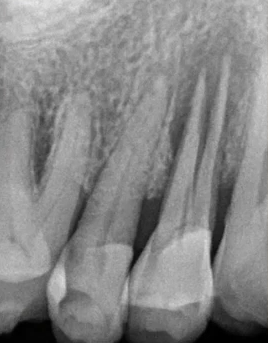

35叩诊(+)

二次拍根尖片确认可看到根尖低密度炎症,临床检查与影像学检查相符,是根尖周炎。

曲面断层片怎么看口腔精读 | 一次性教你看懂曲面断层片!_https://www.jmylbn.com_新闻资讯_第21张